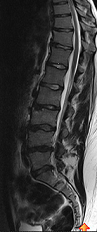

So ich häng euch mal noch mein nettes MRT Bildchen an, damit ihr noch was zum schauen habt (-; und sich der Text evtl nicht ganz so trocken liest.

S.F. Seq.5 T2 TSE SAG 512_CV_3.1.png

S.F. Seq.5 T2 TSE SAG 512_CV_3.1.png (27.32 KiB) 5644 mal betrachtet

general-rammstein, das mit den Bildern hier hab ich noch nicht so drauf :cool:. Das sind definitiv nur breitbasige Protrusionen, da der Faserring noch intakt ist, laut Diskographie (mir wurde allerdings mitgeteilt, das ich aufpassen muss, und eine falsche Bewegung zum Prolaps führen kann).